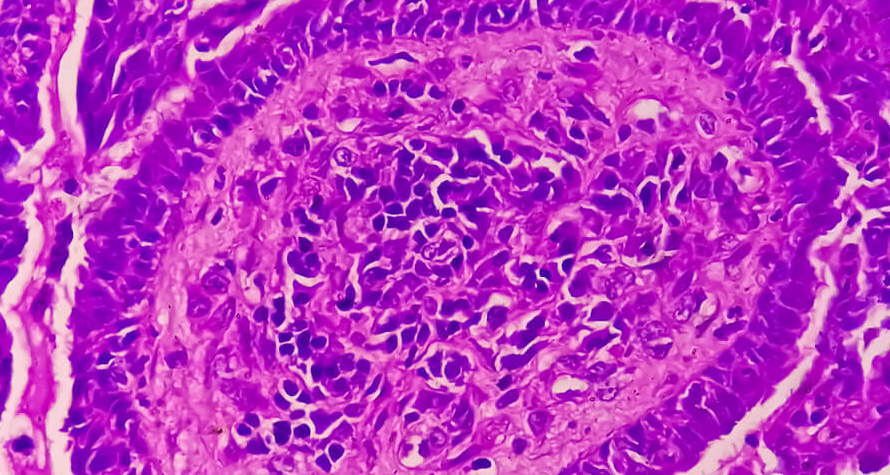

Problem:

Need of making "extra requesting" in complex cases

Solution:

Able to make "extra requesting"

With the IKET Pathologist Network System, pathologists can make requests in complex cases as if they were in the laboratory. IKET Digital Pathologist Networking Platform will also give you an opportunity to work with different specialized foreign pathologists internationally in difficult cases that require "special diagnosis" and will save you time on diagnosis of difficult cases